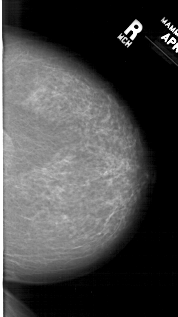

A_1307_1.RIGHT_MLO

RIGHT_MLO LINES 6871 PIXELS_PER_LINE 3811 BITS_PER_PIXEL 12 RESOLUTION 43.5 NON_OVERLAY